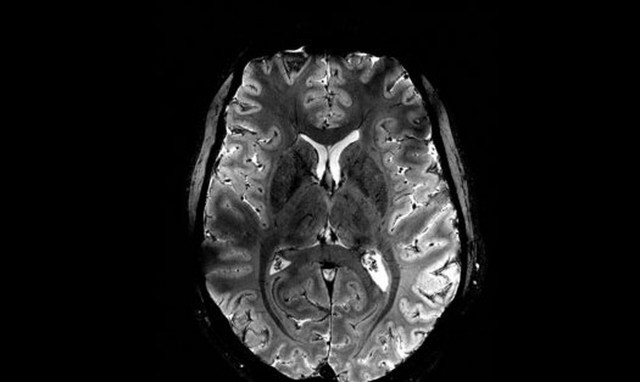

Για πρώτη φορά ζωντανός εγκέφαλος απεικονίζεται καθαρά στον ισχυρότερο μαγνητικό τομογράφο

Σπουδαίο επίτευγμα: Για πρώτη φορά ζωντανός εγκέφαλος απεικονίζεται καθαρά στον ισχυρότερο μαγνητικό τομογράφο

ΚΟΣΜΟΣ · 02.04.2024 - 14:49

Φιλοδοξεί να μελετήσει υγιείς και ασθενείς ανθρώπινους εγκεφάλους με πρωτοφανή ανάλυση